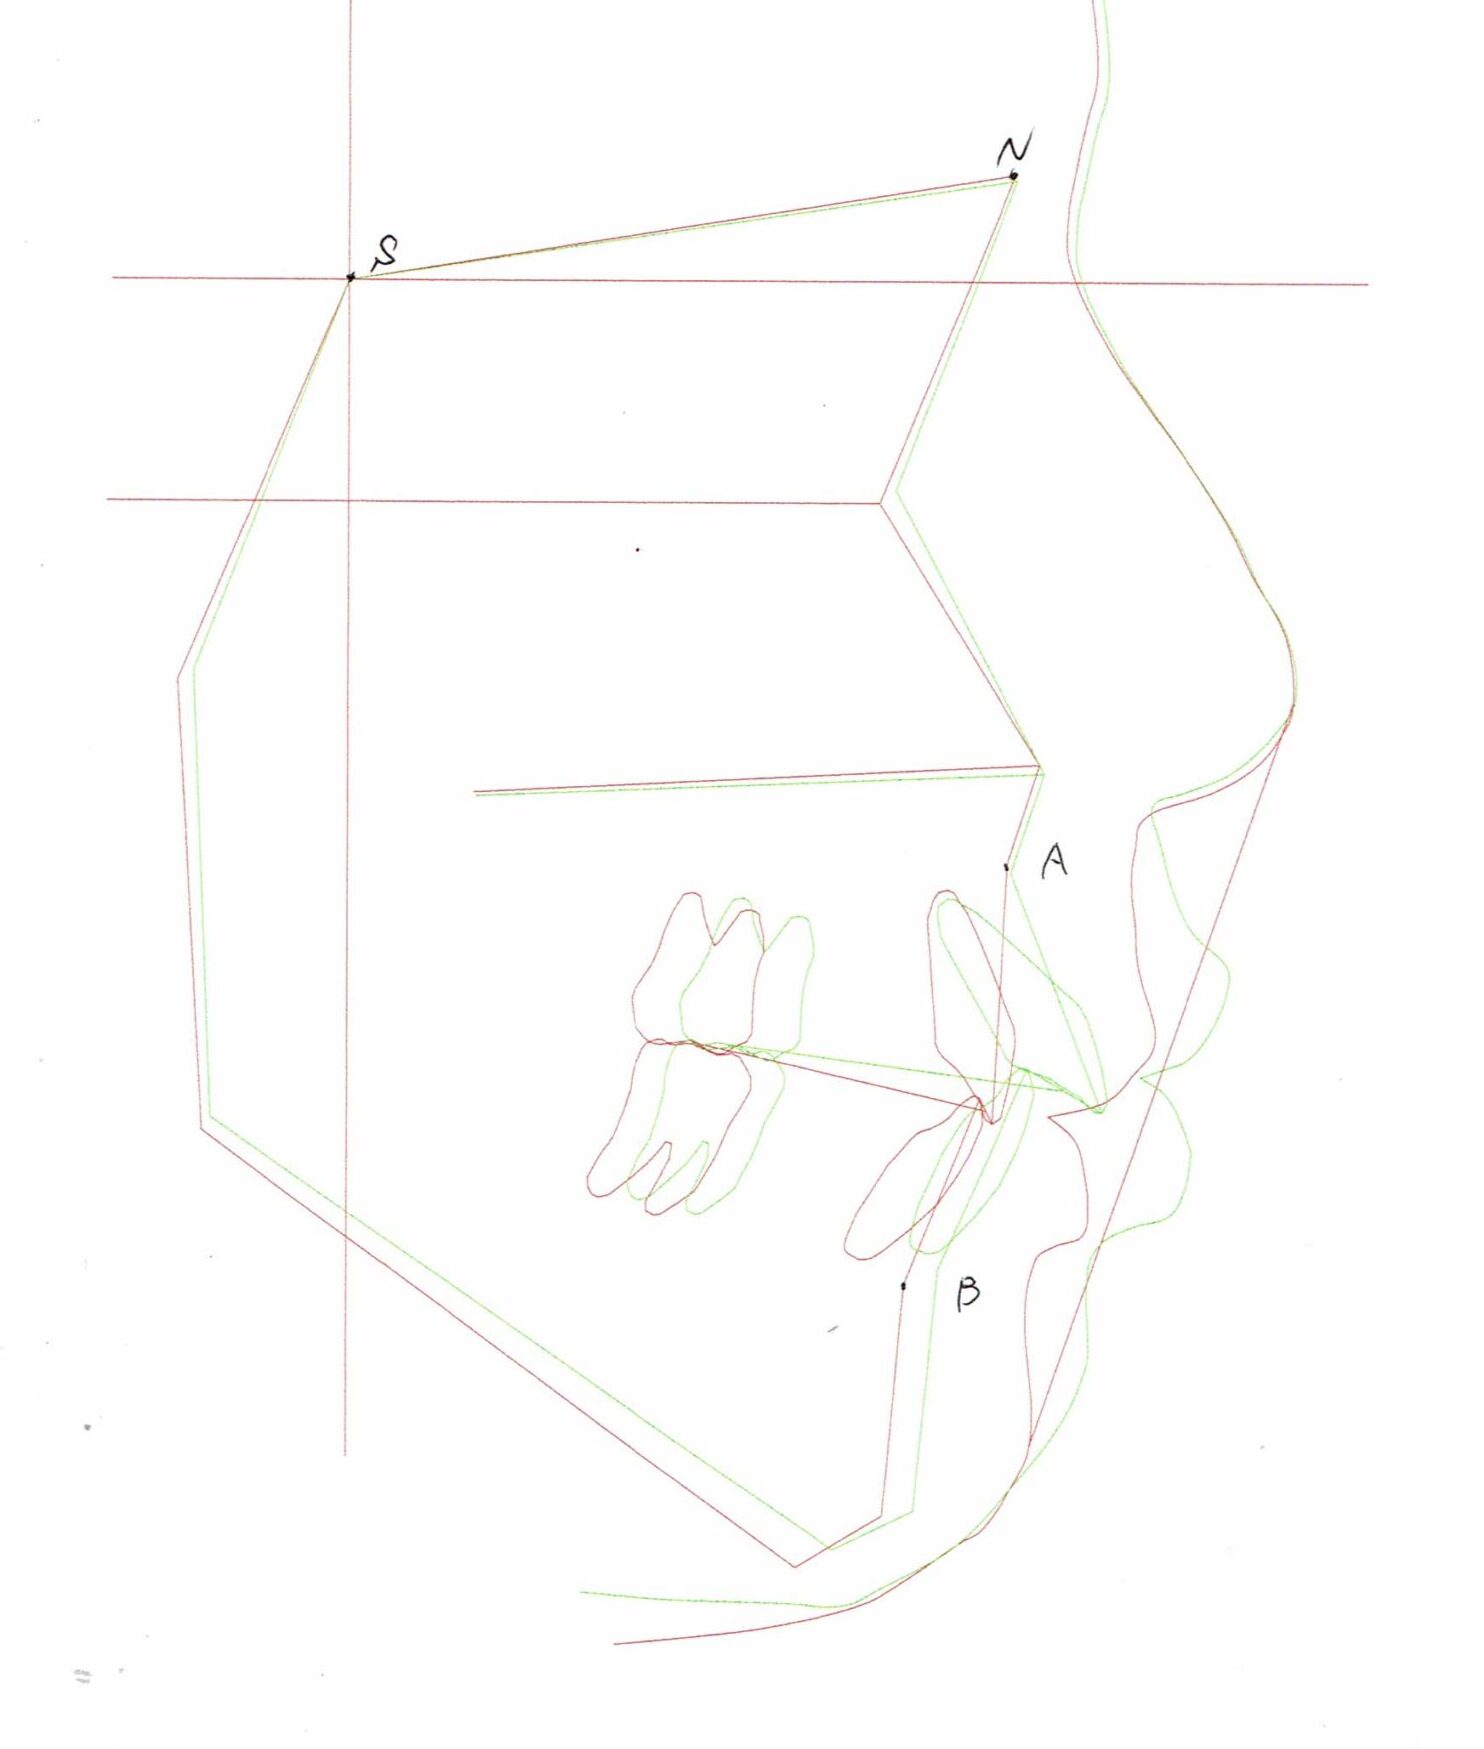

セファログラムのトレースの重ね合わせ(緑:治療前、赤:治療終了時)